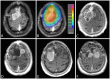

Methods: We characterized 64 temporally- and regionally-distinct specimens from 26 WHO grade III meningioma patients. On initial diagnoses, the meningiomas spanned all WHO grades (3 grade I, 13 grade II and 10 grade III). The tumor samples were screened for TERTp and ATRX/DAXX mutations, and TERT rearrangements. Additionally, TERTp was sequenced in a separate cohort of 19 patients with radiation-associated meningiomas. We examined the impact of mutational status on patients' progression and overall survival.

Results: Somatic TERTp mutations were detected in six patients (6/26 = 23%). Regional intratumoral heterogeneity in TERTp mutation status was noted. In 4 patients, TERTp mutations were detected in recurrent specimens but not in the available specimens of the first surgery. Additionally, a TERT gene fusion (LPCAT1-TERT) was found in one sample. In contrary, none of the investigated samples harbored an ATRX or DAXX mutation. In the cohort of radiation-induced meningiomas, TERTp mutation was detected in two patients (10.5%). Importantly, we found that patients with emergence of TERTp mutations had a substantially shorter OS than their TERTp wild-type counterparts (2.7 years, 95% CI 0.9 - 4.5 years versus 10.8 years, 95% CI 7.8 -12.8 years, p=0.003).

Conclusions: In progressive/higher-grade meningiomas,TERTp mutations are associated with poor survival, supporting a model in which selection of this alteration is a harbinger of aggressive tumor development. In addition, we observe spatial intratumoral heterogeneity of TERTp mutation status, consistent with this model of late emergence in tumor evolution. Thus, early detection of TERTp mutations may define patients with more aggressive meningiomas. Stratification for TERT alterations should be adopted in future clinical trials of progressive/higher-grade meningiomas.